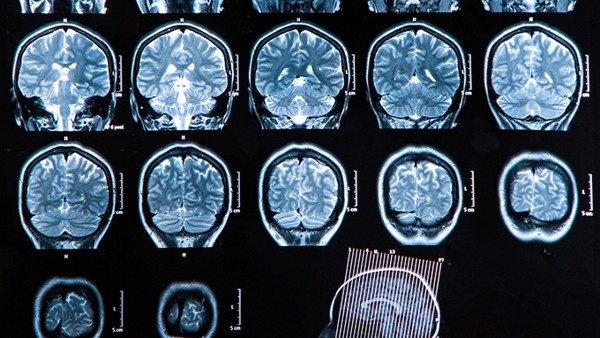

脑出血量的严重性主要取决于出血位置。如果患者的出血位置在幕上,超过30毫升,则更严重。如果出血位置在幕下,超过10毫升,则更严重。这类情况的患者要及时住进神经外科监护室进行治疗,需行开颅手术干预,因为这些部位的出血会导致颅内压增高,容易压迫到脑干部位,进而危害到患者的生命。手术后也需要动态监测患者的生命体征,同时复查头部ct,辅助脱水降压药物治疗。

1、患者的脑出血不管是蛛网膜下腔部位还是脑实质动脉血管破裂引起的出血,都非常危险,其急性期是发病后的一个月内。患者在这段时间若得到合理的治疗,就会进入缓解期,这个阶段病情就比较稳定。